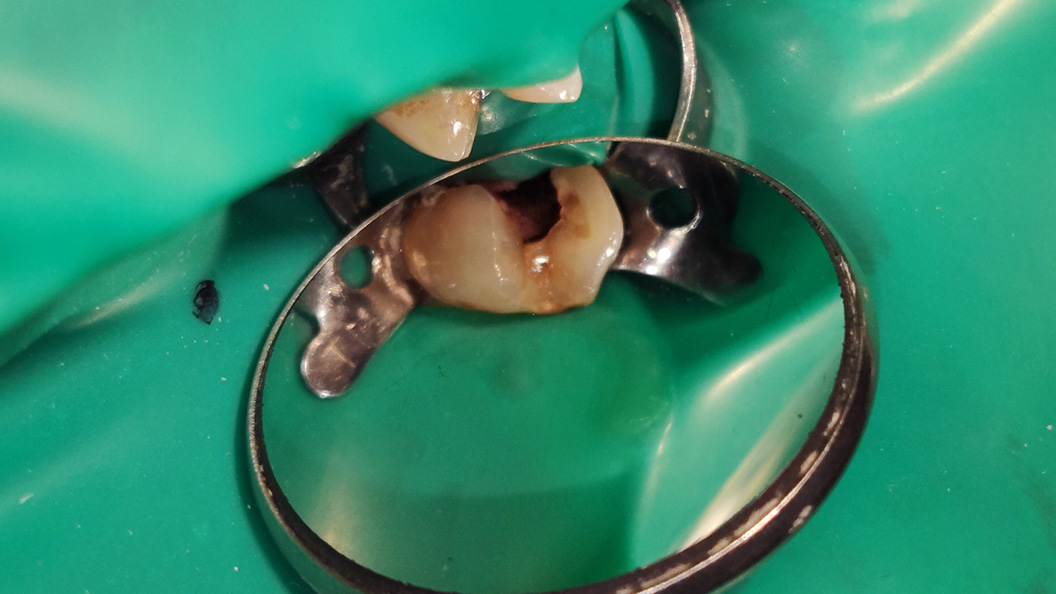

В нашу клинику обратился пациент с жалобами на продолжительные боли в области жевательного зуба на верхней челюсти. Также пациент отметил застревание пищи между зубами и острую болезненную реакцию при приёме холодной и горячей пиши.

В ходе обработки кариозной полости зуба 2.5 под контролем кариес-маркера была вскрыта пульпарная камера, рог пульпы кровоточил. Врач-терапевт Григорьев Пётр Игоревич назначил эндодонтическое лечение зуба с реставрацией коронковой части.

В ходе лечения Петром Игоревичем были проведены следующие работы:

- проведено эндодонтическое лечение зуба 2.5;

- постоянная пломбировка корневых каналов;

- сделана временная реставрация коронковой части зуба.